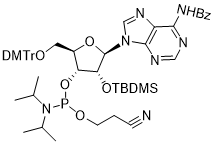

馬鞍山致研生物醫(yī)藥科技有限公司成立于馬鞍山市鄭浦港新區(qū)現(xiàn)代產(chǎn)業(yè)園。公司專(zhuān)注于生物小分子、醫(yī)藥中間體相關(guān)產(chǎn)品的研發(fā)和生產(chǎn),產(chǎn)品主要包括DNA亞磷酰胺單體、RNA亞磷酰胺單體、特殊單體以及按照客戶(hù)要求定制的RNA和DNA,并且公司提供定制合成等方面的研究服...

馬鞍山致研生物醫(yī)藥科技有限公司成立于馬鞍山市鄭浦港新區(qū)現(xiàn)代產(chǎn)業(yè)園。公司專(zhuān)注于生物小分子、醫(yī)藥中間體相關(guān)產(chǎn)品的研發(fā)和生產(chǎn),產(chǎn)品主要包括DNA亞磷酰胺單體、RNA亞磷酰胺單體、特殊單體以及按照客戶(hù)要求定制的RNA和DNA,并且公司提供定制合成等方面的研究服...